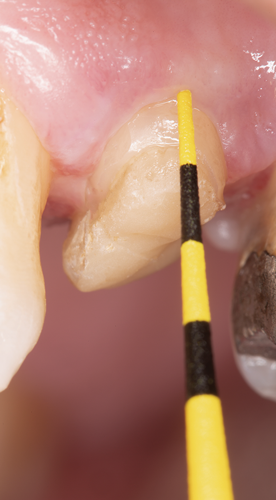

Fig 13. The channel preparation was etched for 15 seconds with 37.5% phosphoric acid semigel.

Figure 13